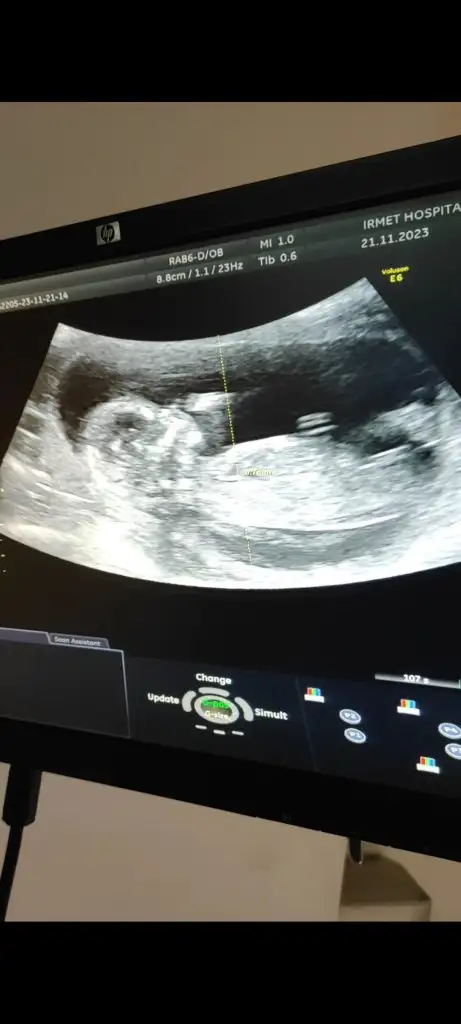

11 hafta olduk bakrmsnTabii atın bakayım, isterseniz buradan isterseniz özelden atın fark etmez

Benimkine de bakabilir misiniz doktorum 11+5te kız dedi 13+6da erkek dediUltrason resmi varsa 11 ile 13 arası nub belli ise bizde tahminde bulunabiliriz

İlk 3 fotoğraf 13+6

Son 2 fotoğraf 11+5

Bu bebek erkek Ahaanda buraya yaziyorum11 hafta olduk bakrmsn

Buda erkekEki Görüntüle 3336350 merhaba banada tahminde bulunurmusunuz13+4 günlük resim bu

Bariz erkek gibi çıkıntısı besbelli 3 çizgi olunca kız diyorlarBenimkine de bakabilir misiniz doktorum 11+5te kız dedi 13+6da erkek dedi